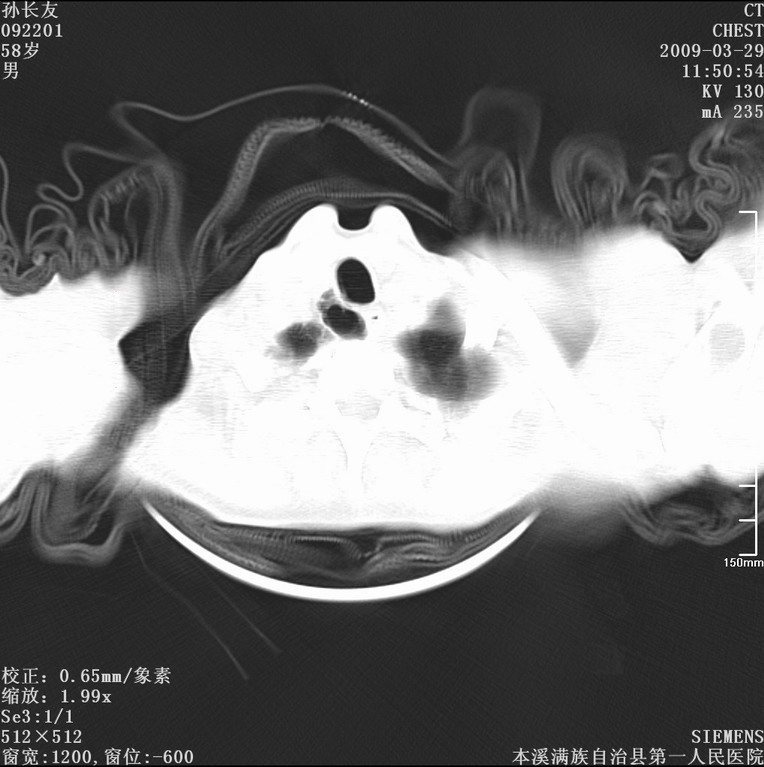

以下是引用liaoqiang在2009-3-30 8:29:00的发言:[br]所上传的层面示气管未见确切异常。